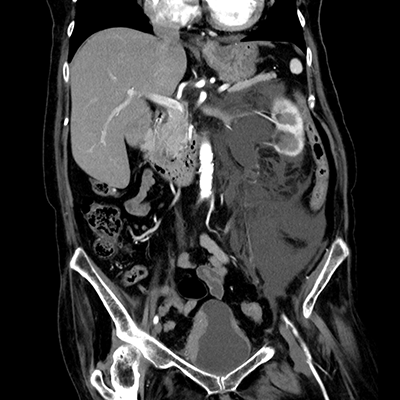

臨床画像例

中山氏 IPVは被ばく低減に役立っています。

当院では、体幹部は平均的にガイドライン*2比で50%近く低被ばくの条件で撮影していますが、読影の先生にも問題なく診断して頂いています。低被ばくに撮影することは、患者さんのメリットに繋がります。当院では、さらに患者さんに安心していただくため、被ばく線量を集計して患者さん向けの説明ツールを作っています。